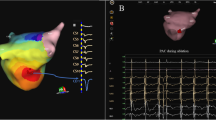

The AcQMap system is a noncontact charge density-based mapping technology that combines ultrasound-based 3D endocardial anatomy reconstructions with high-resolution propagation history maps of electrical activation and allows visualization of global atrial activation. The 48-pole noncontact mapping catheter (AcQMap catheter, Acutus Medical, Carlsbad, CA) has six splines, each spline incorporating eight biopotential electrodes and eight ultrasound transducers. The basket catheter is manually controlled in the mapped atrium. The ultrasound-generated 3D endocardial chamber surface reconstruction corresponds to the end-diastolic size and shape of the atrium and it is created within 2–3 min. Unipolar intracardiac potentials are sensed from the biopotential electrodes of the basket catheter and are processed by an inverse solution to derive the dipolar charge sources at the endocardial surface. The waves of activation are displayed across the 3D anatomy reconstruction through time as high-resolution propagation history maps. The noncontact modality of the AcQMap system allows for two modalities of mapping: single position mapping (SPM) and aggregated multiposition noncontact mapping (AMPM). SPM can be applied as single-beat analysis to map short non-sustained ATs or PACs (Fig. 1 and 2). While AMPM enables mapping of both non-sustained and sustained repetitive atrial rhythms (Video 1). After hovering the basket catheter around the cardiac chamber, multiple noncontact catheter positions are time aligned based on coronary sinus (CS) activation (Fig. 3). The utilized mapping modality was chosen at the discretion of the operator if the arrhythmia lasted long enough. In cases of short-lived ATs and PACs only SPM was possible.

– SPM versus AMPM. Two separate cases of AT, both mapped with SPM and AMPM, too. In Panel A the SPM shows the exit of the isthmus, the propagation in CCW direction and no retrograde conduction because of the line, which contains the isthmus. However, the signal of the isthmus itself (conduction through the isthmus) is only visible on the AMPM. In panel B the SPM isochronal map shows less detail (circle), compared to the AMPM on the right, the yellow arrow shows a more detailed localization